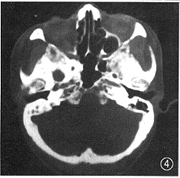

图4 右侧卵圆孔扩大

2.肿瘤CT表现:(1) 大小为1.5 cm×1.0 cm~6.7 cm×6.5 cm;(2) 密度为较密集的小囊状低密度改变组成的筛样结构21例(图1),均匀密度7例,部分筛样、部分均匀密度5例;(3) 形态无定形20例(图2),类圆形11例,长条形与多结节形各1例;(4) 边缘不清晰20例,清晰13例,是由于周围正常脂肪组织环绕对比所引起;(5) 特殊改变:发生在气管的3例中,均表现为肿瘤绕气管腔后壁及两侧壁生长,以后部为主,管腔受压变形,但气管黏膜面仍保持光整(手术证实),甲状腺向两侧推移并均有累及(图3)。腮腺5例,同侧面肌和(或)颊肌呈萎缩改变者3例。发生在腭、鼻腔鼻咽、上颌窦等处肿瘤易侵犯翼腭窝向颅内浸润且合并颅底骨质破坏(5/10),其中侵犯中颅窝卵圆孔3例,表现为卵圆孔扩大或局部骨质破坏,同侧翼肌及咬肌萎缩(图4,5)。本组仅1例作MRI检查,发现肿瘤沿神经侵犯,表现为神经增粗(图6),此改变在CT上无法表现。